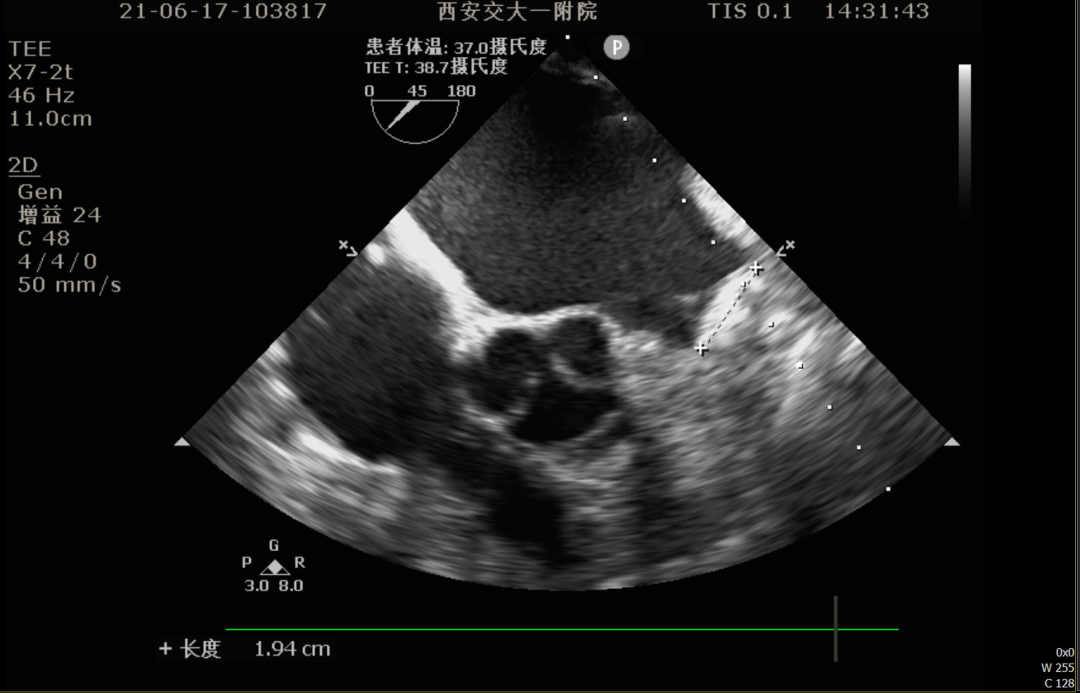

术前TEE评估

术前排除左心耳血栓,左心耳可能呈反鸡翅型,心耳偏小,梳状肌发达。

0°TEE

TEE测量左心耳数据:

TEE测量结果:

该患者左心耳开口较小,呈反鸡翅型,开口处即反折,同时内部梳状肌发达,且深度较浅,因此手术难度偏大,术前安排进一步CT评估以协助制定手术策略。